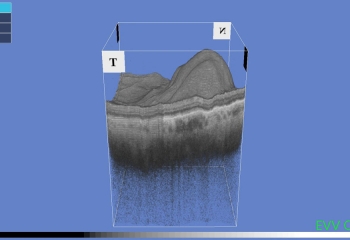

• Liquido o depósitos grasos en la retina y especialmente sobre la macula

• Desprendimiento de retina